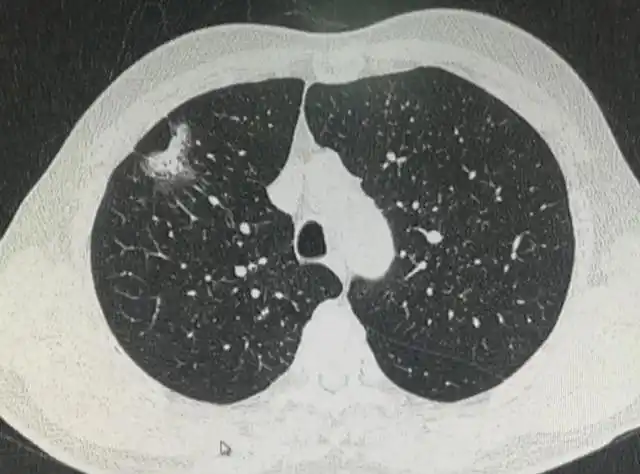

肺结节怎么治疗

5.8):存在了2年的实性结节,我为什么叫他开刀?

查出肺结节,怎么确定是不是恶性结节?

病例分享右肺多发结节良性的切了恶性的却留下了